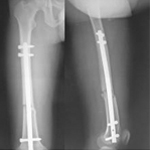

張某,男,50歲,因“左股骨骨不連”入院。植骨+PRP治療后8月完全愈合。

術(shù)中

02.jpg